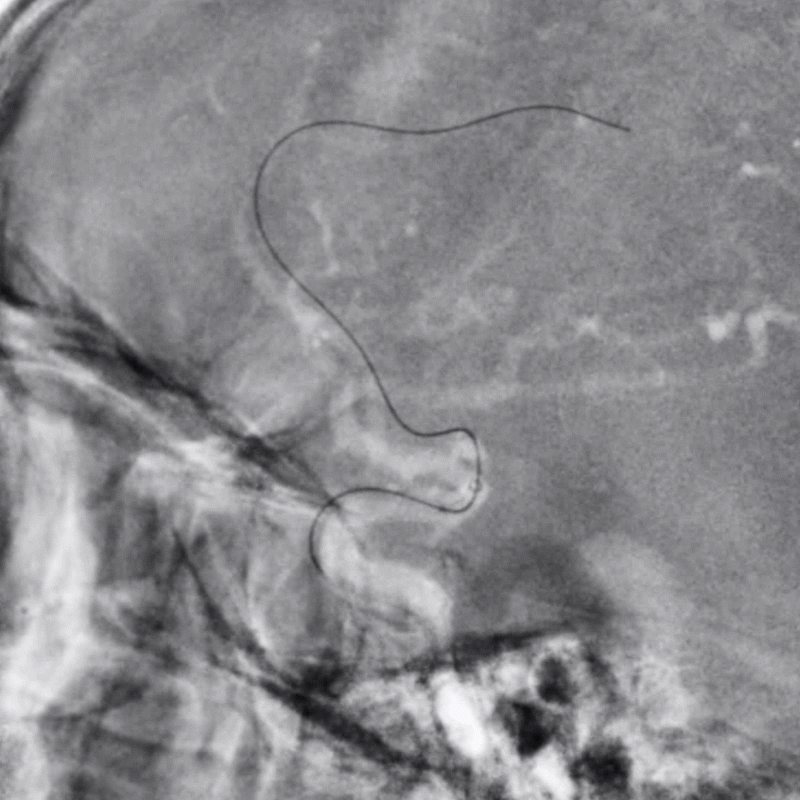

长鞘+125cm单弯+加硬导丝建立通路;Tethys®中间导引导管+0.014inch微导丝+10微导管。

导丝通过病变段。

微导管跟进。

确认系统位置,交换3m 0.014inch微导丝。

加奇1.75mm×9mm SacSpeed®球囊扩张导管顺利到位。

缓慢扩张。

扩张后前向血流仍较差。